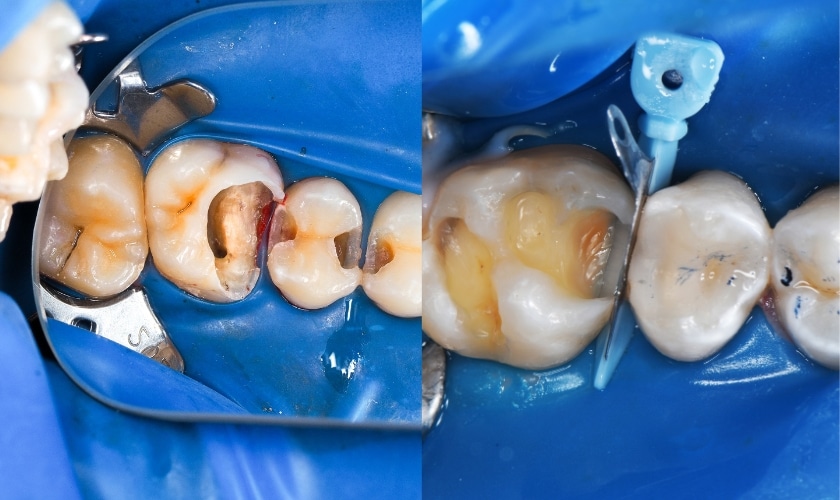

Findings from the images: Rubber dam isolation with matrix bands in place; multiple deep occlusal-/proximal caries excavations on posterior teeth. Some restorations are in progress — there is close proximity to the pulp on at least one surface. Tooth structure shows large cavities with thin remaining walls.

Most likely diagnosis: Moderate → deep dental caries (proximal and occlusal) with very high risk of pulpal involvement. One or more teeth may have reversible or irreversible pulpitis depending on symptoms and whether the pulp has been exposed during excavation.

Isolation & caries removal (rubber dam already placed in images) — remove infected dentin, preserve sound tooth structure.

Current images show appropriate isolation and restorative technique underway — this is good practice. However, because cavities are deep and very close to the pulp, careful pulp assessment is critical. If the pulp was exposed during excavation, immediate pulpal treatment (direct pulp capping only if small exposure in a young tooth and conditions ideal) or RCT is needed. Conservative care prevents escalation to extraction.